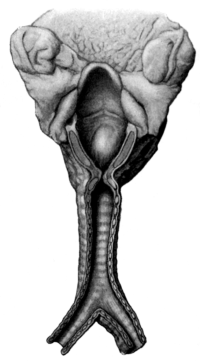

| 54. | Chronic Uterine Inversion | 151 |

Ovariotomy signifies the removal through an abdominal incision of cystic and solid tumours of the ovary, and parovarian cysts.